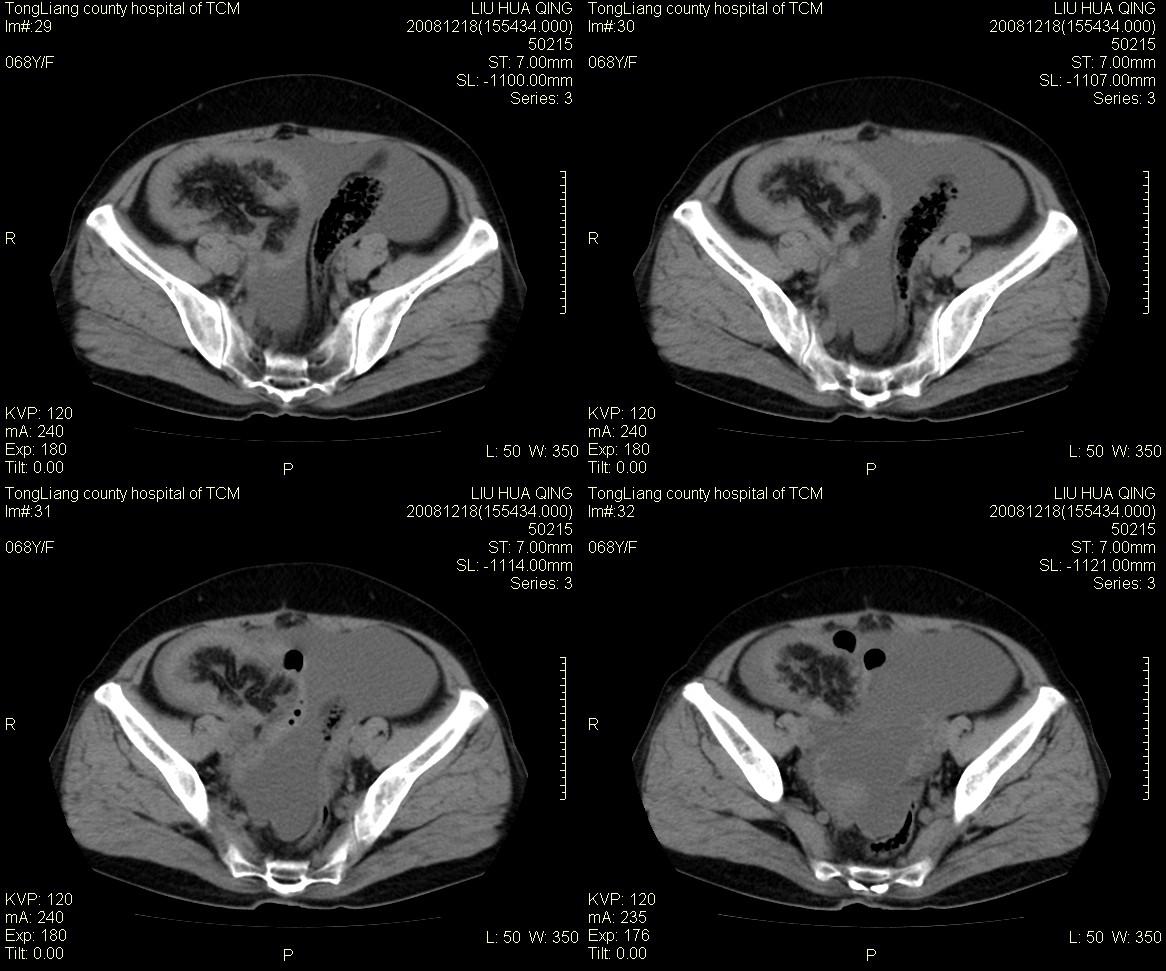

女,68y,下腹疼3月,一月半前院外ct示上腹未见异常。近1月来,症状加重。4天前入院,b超示胸腹水。今日呕吐频繁。  生化检查:  结核抗体阴性,血沉18mm/h, 癌胚抗原阴性,胸水细胞学检查见多数淋巴细胞。 白细胞总数5.4x10^12/l,血红蛋白104g/l.

患者右中腹部肠管聚集,内密度不均,可见片絮状及结节样增密影,小肠壁增厚,与之相邻处有软组织影。

肠系膜可见梳征,不除外克罗恩氏病.腹水,建议气钡双重造影,灌肠.

1)右侧腹腔前部见类似“网膜饼”样改变,考虑网膜转移瘤。2)腹水。

腹膜污染[大网膜增厚可见污垢征及小班结与饼片影,肠系膜增厚],大量腹水。考虑癌性腹膜炎,建议查腹水。结核待排.注意上腹部及胃肠道检查